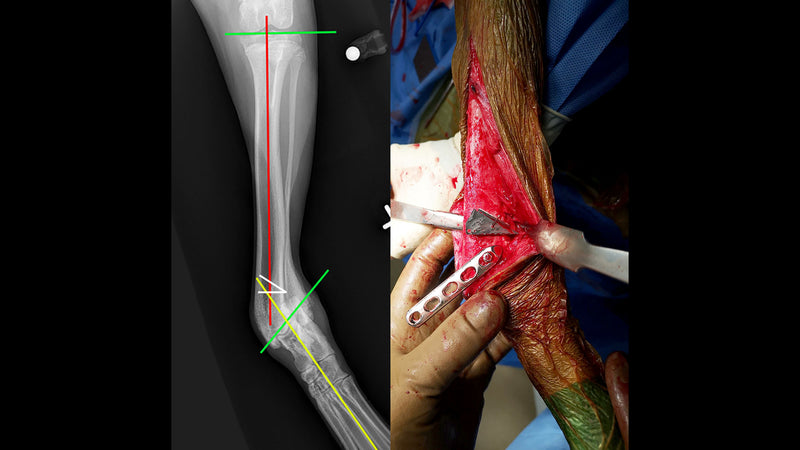

These wedge osteotomy guides are designed to provide increased accuracy while simplifying the corrective osteotomy procedure. Guides include a hole for organization onto a small plate clip or wire loop. Temporary k-wires are supported through a separate 0.9 mm (0.035") hole.

The small guide tab is placed into the initial (partial) osteotomy while the larger tab is used for matching the saw blade orientation to the selected angle.

Correction of angular limb deformities in small animal patients can be challenging and begins with detailed planning of the correction which often involves a closing wedge ostectomy.